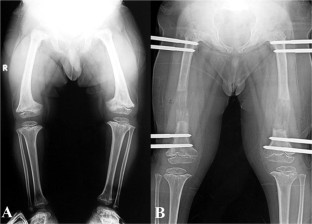

Fig. 2